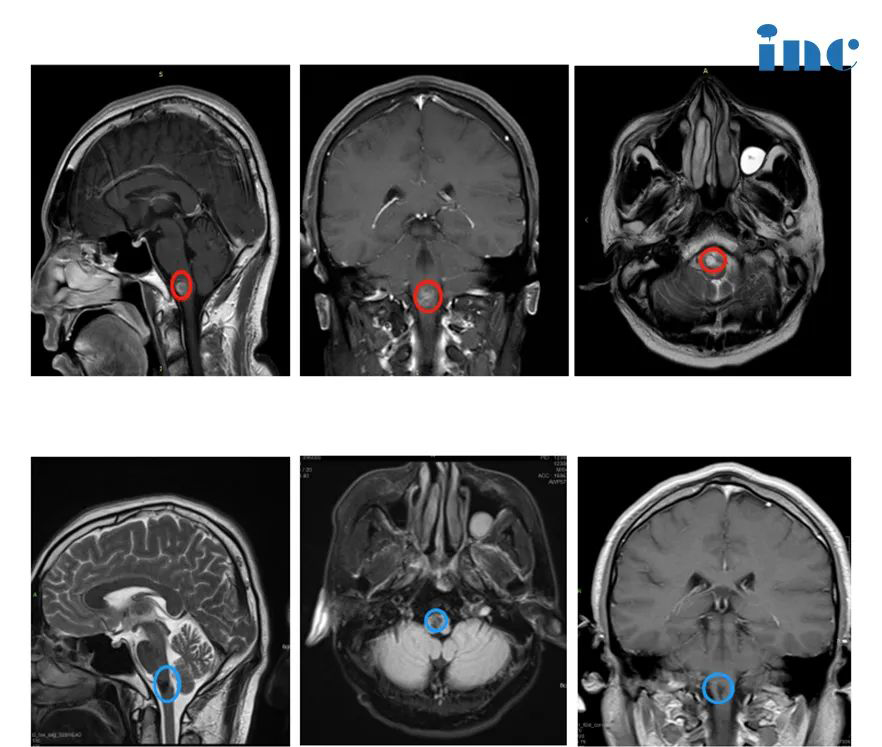

2.18岁小杰,颅咽管瘤

18岁小杰,本该青春正好的年纪,他却饱受颅咽管瘤折磨,10多年内三次手术、四次复发。所幸,他较后找到INC德国巴教授全切颅咽管瘤,术后的他恢复状态良好,无任何神经功能损伤,如今术后一年多过去了,小杰未见肿瘤复发,早已回归了正常生活。

“我以前在国内手术过,不是一开始做手术了,两年就复发了。这是一,二呢我们是在欧洲,移民到欧洲的。那么去德国对我们来说,一个是更方便,二个德国的那种对外的这种水平啊、名气啊,我相信还是很的。所以我选择去德国做手术。我觉得巴教授医术和人品太让我敬佩。术后我出于患者的家属关心手术情况的,我就想问下手术情况怎么样。他虽然术后那么疲倦,依然很耐心得给我们讲解,所以我真的是很感动。”——小杰的妈妈。